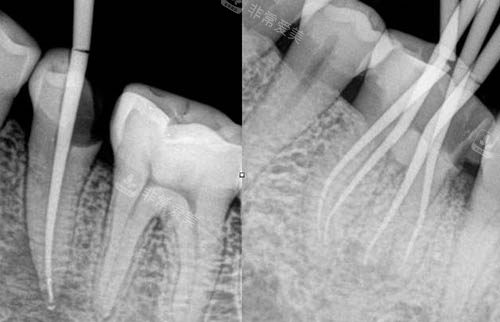

根管治疗的核心在于深度清除感染、严密填充根管,这高度依赖医生的技术和设备的新型性。雅馨口腔在这方面的投入很实在。他们能够开展牙体牙髓显微根管治疗,简单说,就是医生在高倍显微镜下操作,视野被放大几十倍,那些肉眼看不见的细小、弯曲的根管都能看得一清二楚,清理得更深度,大大降低了治疗残留和复发风险。

同时,医院采用的智能化根管治疗技术和口腔CT等靠前的设备,在治疗前就能为牙齿进行“三维扫描”,让医生更准一些掌握根管的数目、形态和病灶范围,制定出更个体化的方案。这种硬件配置,为治疗的成功几率和远期结果提供了扎实维持。